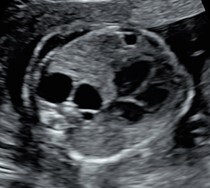

La CPAM viene agevolmente diagnosticata mediante l’esame ecografico in cui appare come un’area iperecogena disomogenea con all’interno possibili aree cistiche anecogene di diverse dimensioni, contenenti liquido. Tra le diverse classificazioni esistenti, quella attualmente più utile in ambito ecografico soprattutto per il suo significato prognostico, distingue le forme di CPAM in macrocistiche e microcistiche.

Immagini ecografiche di CPAM di tipo macrocistico (A), microcistico (B) e misto (C)